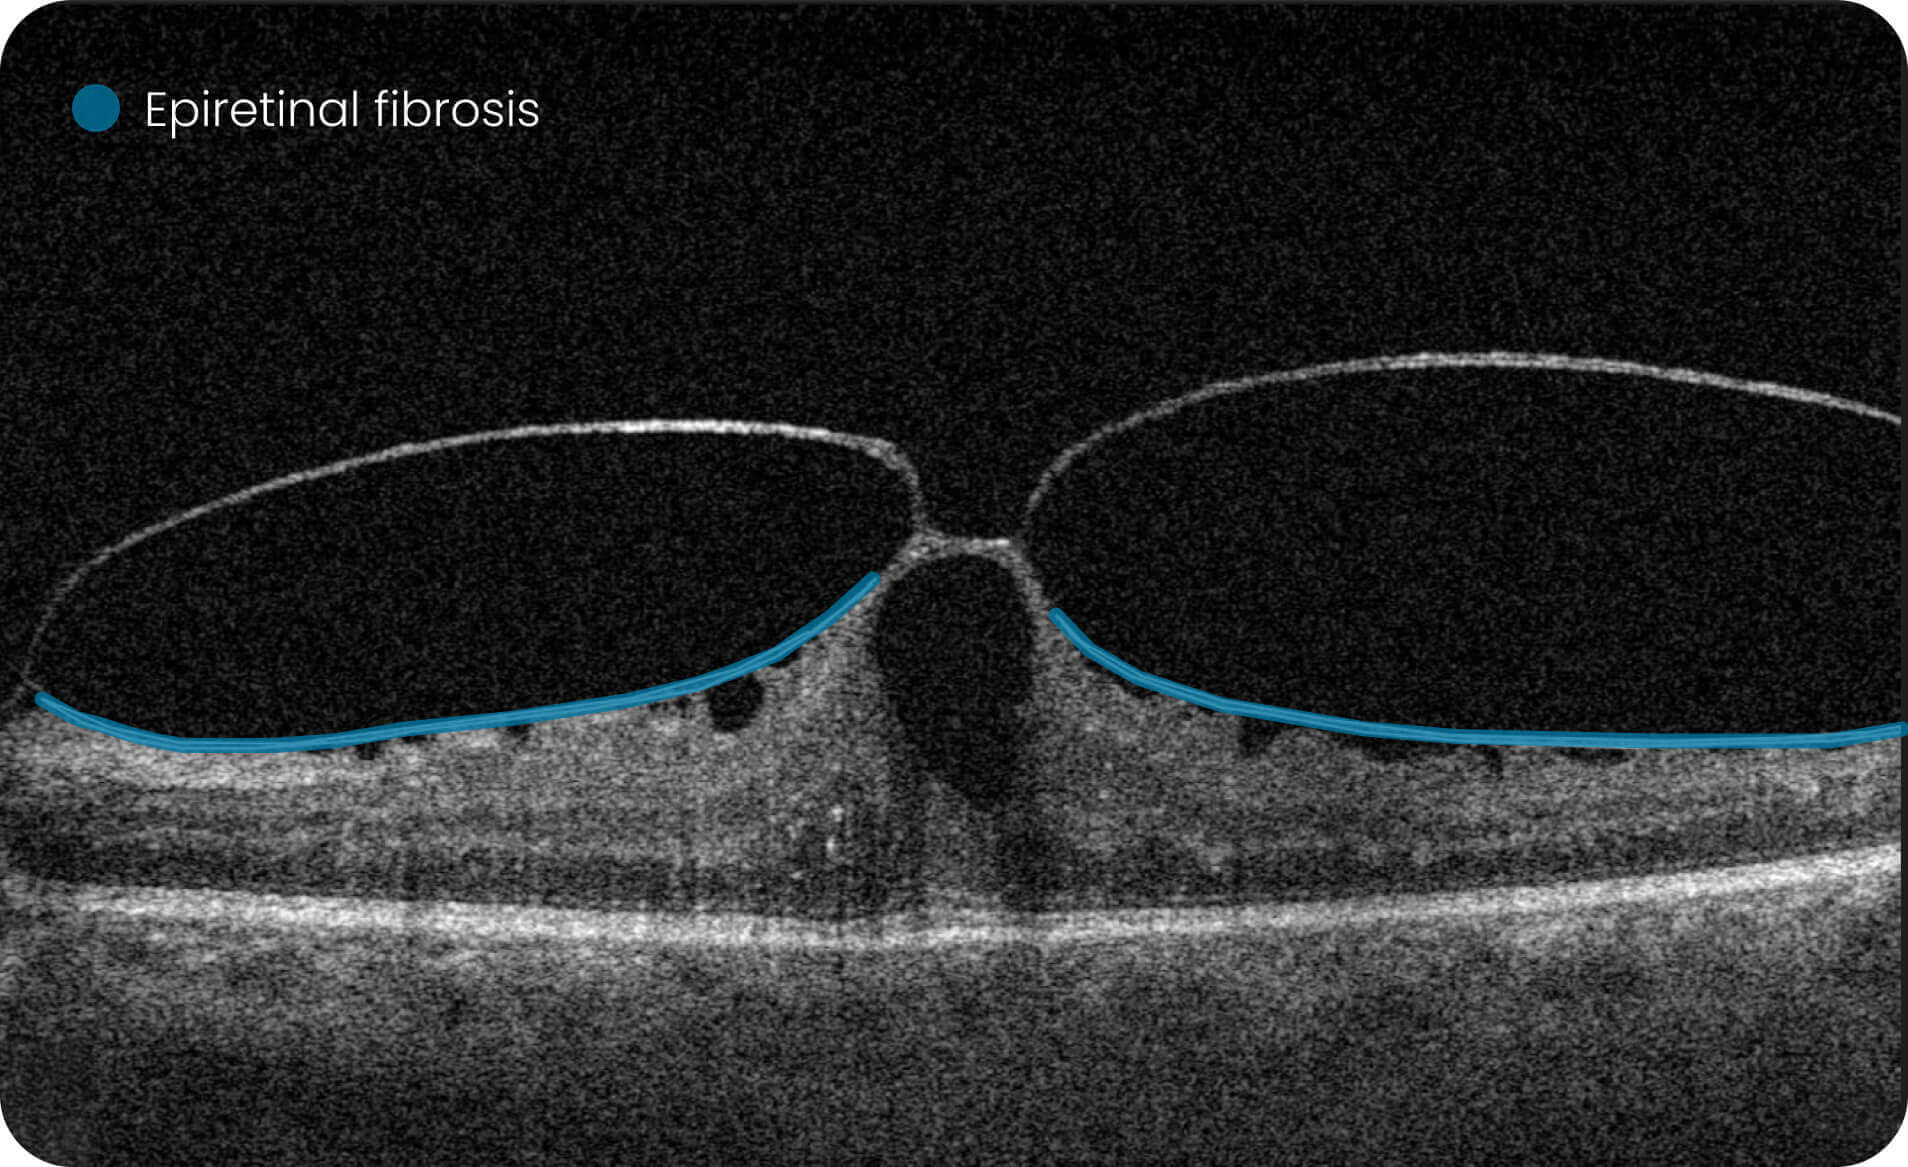

The AI wet age-related macular degeneration in USA platform supports visualization and quantitative, image-derived characterization of OCT imaging features commonly associated with Wet AMD, presented with spatial context on ETDRS-style grids and B-scan views.

Altris AI Models  Research Use Only (RUO). Not for use in diagnostic procedures. These tools enable quantitative, algorithmic exploration of OCT data for research and analytical purposes, including the study of over 40 retinal biomarkers and more than 30 retinal conditions, such as Wet AMD.

• Annotate and explore OCT images for research purposes.

• Quantitative measurements of retinal biomarkers, fluid volume, and drusen count for investigational/analytical purposes only.

Investigation of 40+ retinal biomarkers and 30+ retinal conditions, such as Wet AMD